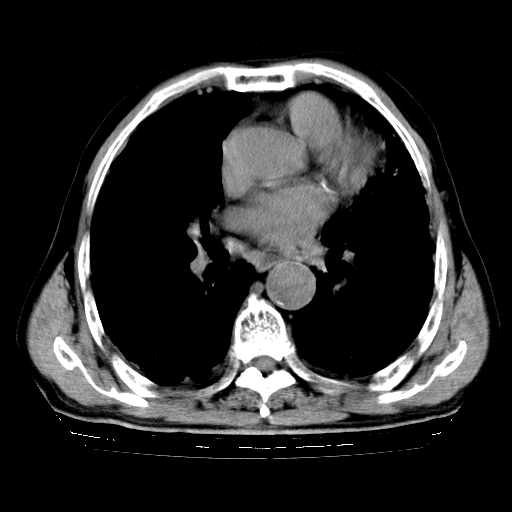

标题: CT25149:男,69岁,反复咳嗽、咳痰五年余,呼吸困难三天。 [打印本页]

男,69岁,反复咳嗽、咳痰五年余,呼吸困难三天。

慢支伴感染、肺气肿、肺心病

慢支伴感染、肺气肿、肺心病!支持!另:间质纤维化!

慢支伴感染、肺气肿、肺心病。双肺间质性改变(间质纤维化)。